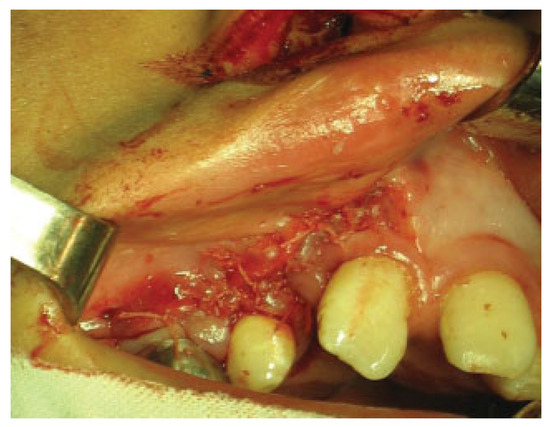

Alveolar bone grafting was performed under general endotracheal anesthesia. Incisions were made and gingival mucoperiosteal flaps were elevated in the standard fashion for alveolar bone grafting to create a suitable pocket (►Figure 1).

Figure 1.

Elevation of gingival mucoperiosteal flaps and dissection of the pocket.

On the vestibular side, the incision is made along the gingival border to ensure that the gingival flap contains the required width of attached gingiva. Posteriorly, the incision is extended to the first permanent molar where it is angled up into the sulcus. To provide sufficient mobility, it is often necessary to cut through the periosteum at the base of the flap. Anteriorly, the incision is extended to the mesial aspect of the cleft. Vertical incisions are made along the edges of the cleft. Wide exposure of the cleft area is achieved through these incisions. On the palatal side, mucoperiosteum is lifted off the bone in the cleft region and off the frontal and lateral segments of the maxilla. All soft tissues are carefully stripped off the residual alveolar cleft. The nasal mucoperiosteum is pushed upward, and if a fistula is present, the nasal floor is reconstructed. On the palatal side, mucoperiosteal flaps are raised along the edges of the cleft, and usually the margins are trimmed to fit together before suturing with everting mattress sutures. The alveolar cleft is now delimited by denuded bone medially and laterally and by the raw surface of mucoperiosteum on the nasal and the palatal side.